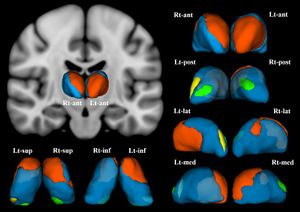

Publication: PLoS One. 2018 Dec 19;13(12):e0208152. PMID: 30566534 | PDF Authors: Asami T, Yoshida H, Takaishi M, Nakamura R, Yoshimi A, Whitford TJ, Hirayasu Y. Institution: Department of Psychiatry, Graduate School of Medicine, Yokohama City University, Yokohama, Japan. Abstract: The thalamus is believed to play crucial role in processing viscero-sensory information, and regulating the activity of amygdala in patients with panic disorder (PD). Previous functional neuroimaging studies have detected abnormal activation in the thalamus in patients with PD compared with healthy control subjects (HC). Very few studies, however, have investigated for volumetric abnormalities in the thalamus in patients with PD. Furthermore, to the best of our knowledge, no previous study has investigated for shape abnormalities in the thalamus in patients with PD. Twenty-five patients with PD and 25 HC participants (all female) were recruited for the study. A voxel-wise volume comparison analysis and a vertex-wise shape analysis were conducted to evaluate structural abnormalities in the PD patients compared to HC. The patients with PD demonstrated significant gray matter volume reductions in the thalamus bilaterally, relative to the HC. The shape analysis detected significant inward deformation in some thalamic regions in the PD patients, including the anterior nucleus, mediodorsal nucleus, and pulvinar nucleus. PD patients showed shape deformations in key thalamic regions that are believed to play a role in regulating emotional and cognitive functions. Funding:

Female patients with panic disorder showed significant inward deformation of shape in the bilateral thalamus compared with female healthy control subjects (false discovery rate corrected, P < .05). These regions included (in the right thalamus) the anterior nucleus, medial mediodorsal nucleus, and lateral posterior nuclei (orange), and the medial part of pulvinar nucleus (green). In the left thalamus, the anterior nucleus, ventro-lateral nucleus, ventral anterior nucleus (orange), the medial part of pulvinar nucleus (green), and the lateral part of pulvinar nucleus (yellow) were affected. Abbreviations: Rt, right; Lt, left; ant, anterior view; post, posterior view; lat, lateral view; med, medial view; sup, superior view; inf, inferior view; 3D images were created using 3D Slicer. |